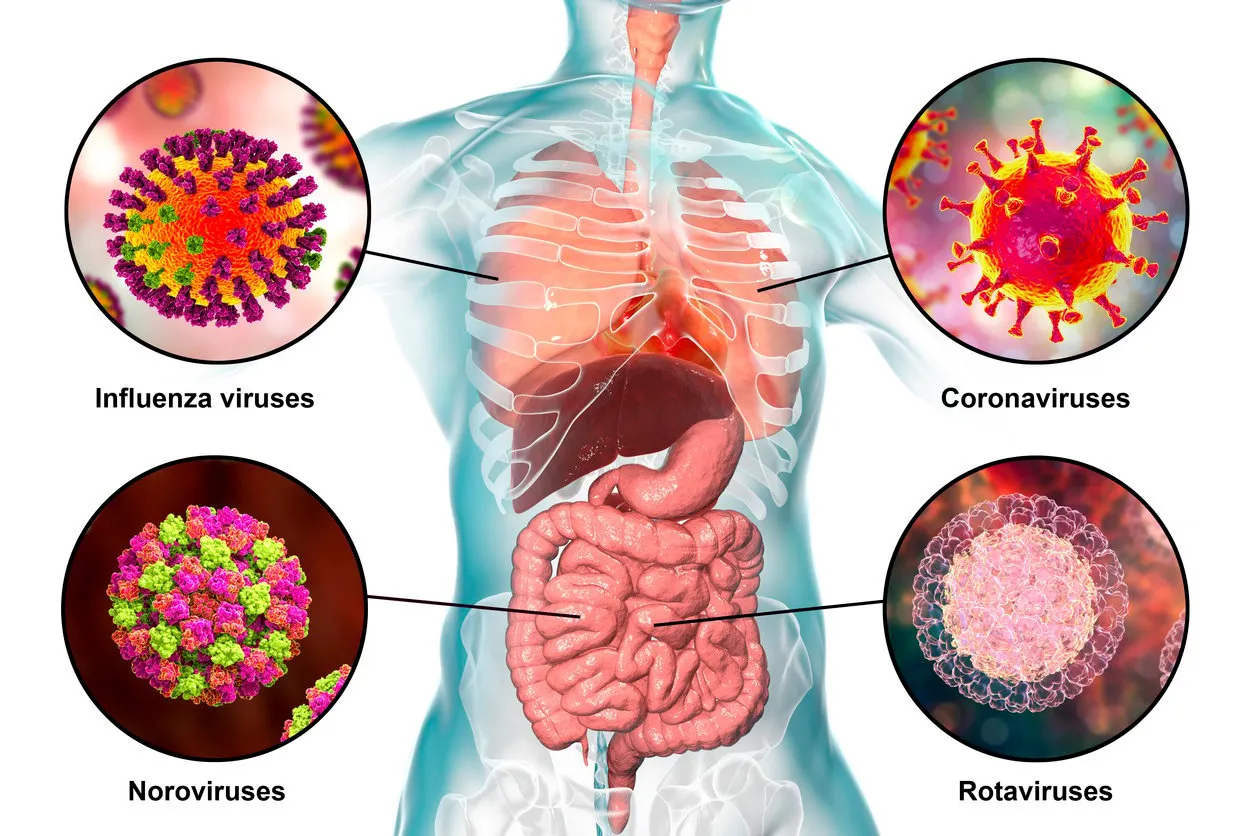

Photo : virus pathogènes provoquant des infections entériques et respiratoires